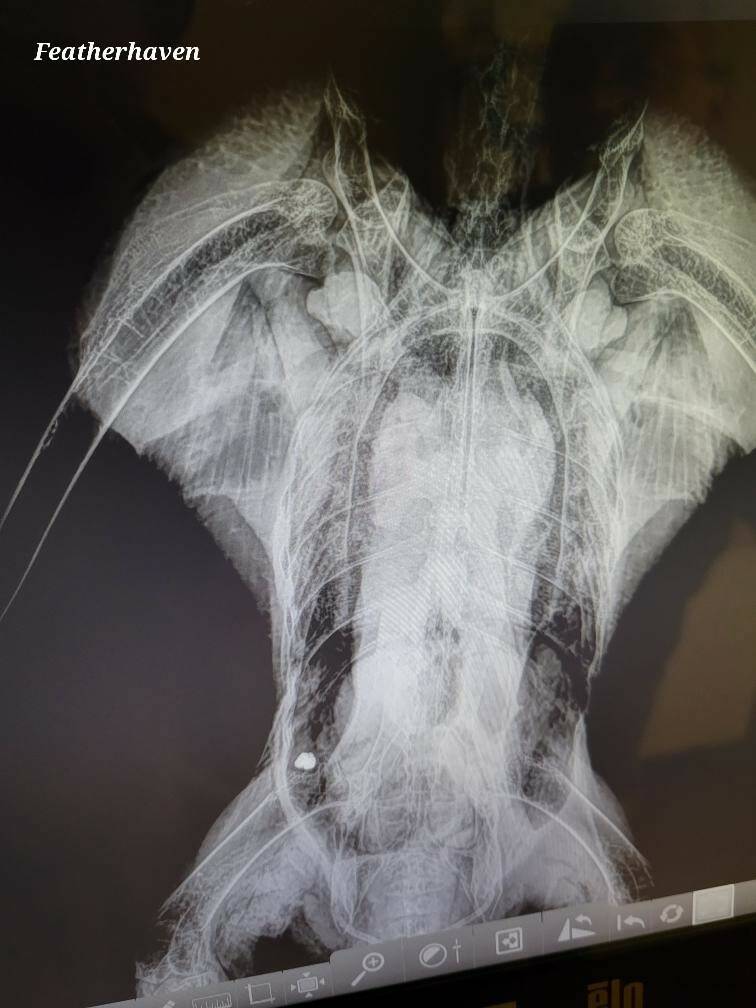

The bullet that struck the bald eagle was deformed, which could mean it hit the bird’s spine and paralyzed it. Photo by Featherhaven/David Ward

“We found… a wound in the right ventral shoulder, fresh,” Ward said. “We did a series of X-rays, which showed [a] bullet in the caudal abdomen on the right side.”

The bullet was deformed, which can be caused when it comes into contact with soft tissue, Ward continued — but more than likely, it hit the spine, causing the eagle to be paralyzed from the proverbial waist down.

It was determined by Ward and two other experts that the chances of the eagle recovering was extremely low — “way less than 5%,” he said, given that nobody present was specialized in bald eagle spinal surgery — so it was humanely euthanized that evening.